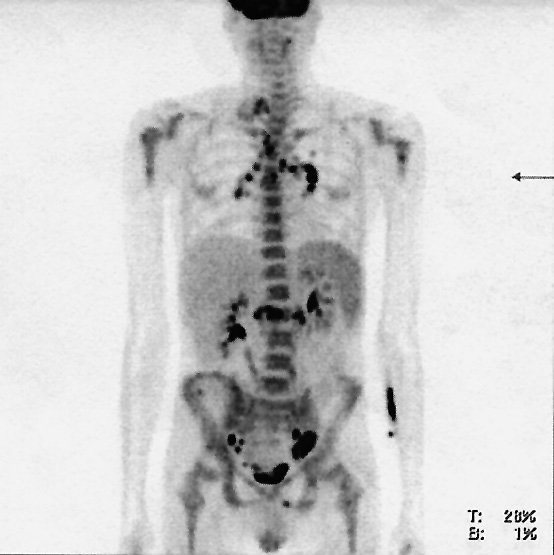

При плановом контроле ПЭТ-КТ через 3 мес после окончания лучевой терапии была выявлена прогрессия заболевания в виде множественного поражения лимфоузлов с максимальным накоплением SUVmax до 11, многоочаговым поражением ткани легких, костей и диффузным поражением селезенки (рис. 3). Клинических симптомов не отмечалось. Прогрессирование заболевания было подтверждено морфологически по данным биопсии шейного лимфоузла.

Рис. 3. Прогрессирование заболевания по результатам ПЭТ-КТ (поражение левых шейных, единичных внутригрудных, единичных забрюшинных лимфоузлов, множественные очаги в легких и селезенке, в ости правой лопатки, в позвонках (ThIV, ThX–ThXII, LII, LIII, LV), в VI и VIII ребрах справа, костях таза, в проксимальном диафизе левой бедренной кости).